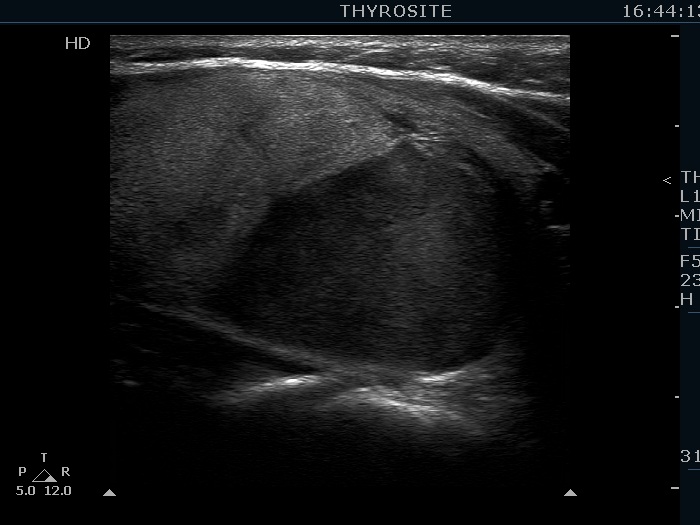

The echogenicity of the nodule - case 2158

Examination 3 years later (ultrasonographic picture 5)

Right lobe, another longitudinal scan.